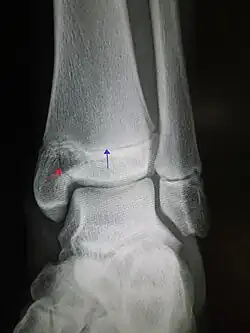

An X-ray of the left ankle showing a Salter–Harris type III fracture of medial malleolus. Red arrow demonstrates fracture line while the blue arrow marks the growth plate. | |

- Type III – A fracture through growth plate and epiphysis, sparing the metaphysis:[9] 8% incidence